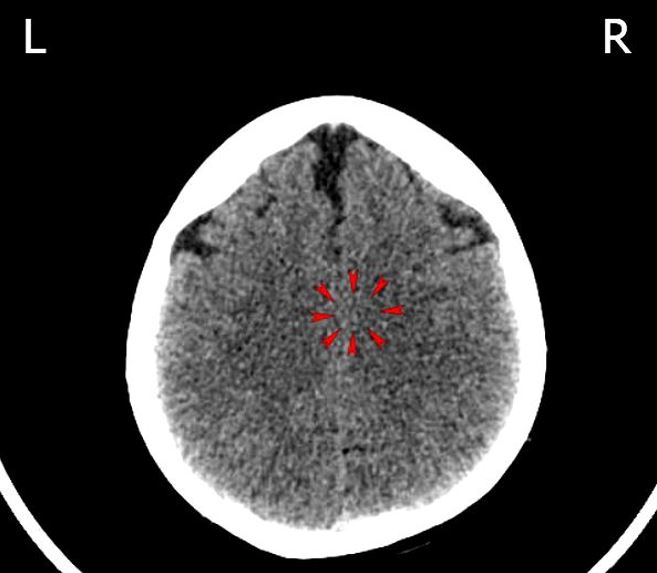

Hier sind Auszüge von den Briefen, die ich an Dr. Hamer schrieb. (Er hatte damals mein Gehirn-CT angeschaut und mir gesagt, dass es sich um ein intraduktales Geschehen handelt. Als ich sagte, dass hier nur Tischkas Tod in Frage kommt, war er wegen der doch sehr langen Konfliktdauer zuerst nicht sicher, aber ich hatte ja auch ein CT von 2015, das ich kurz nach Tischkas Tod gemacht habe. Damit konnten wir den Konfliktverlauf verifizieren, da im CT von 2015 ein aktiver HH für die linke Brust zu sehen ist):

Das letzte CT aus dem Jahr 2020 bestätigt diese Vermutung, aber zum Glück haben wir für solche Fälle „Mein Studentenmädchen“, das die Verfasserin des Erfahrungsberichts weiterhin täglich hört, besonders durchgehend nachts.